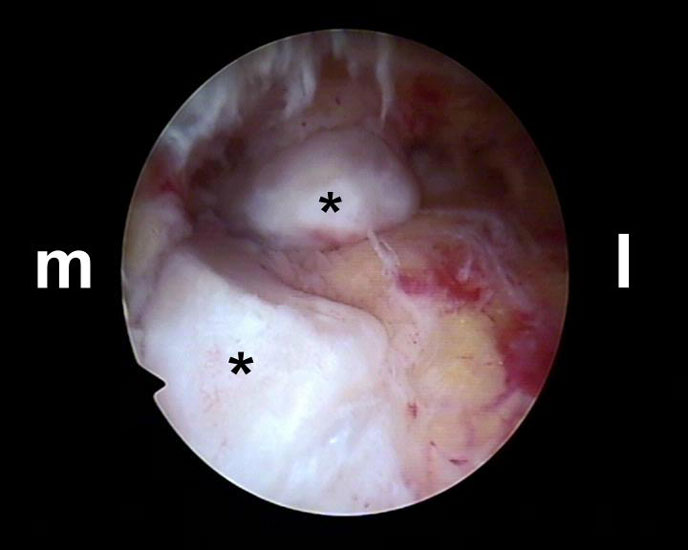

Abbildung Nr. 8-10

Es wird zunächst ein Weichteildebridement durchgeführt, bis die Flexor hallucis longus-Sehne identifiziert werden kann. Während des Debridements sollte auf die korrekte Ausrichtung der Instrumentenöffnung nach lateral geachtet werden. Im Verlauf empfiehlt sich der Wechsel auf eine bipolare Ablationselektrode, die eine gezielte Freilegung der Strukturen unter gleichzeitiger Blutstillung ermöglicht, ohne dabei unkontrolliert Gewebe anzusaugen (rechte Seite, m=medial, l=lateral). Das Os trigonum bzw. die Osteophyten sowie die FHL-Sehne müssen vollständig dargestellt werden (*=Os trigonum, FHL=Flexor hallucis longus-Sehne).